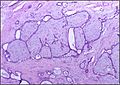

Histopathologic image of breast fibroadenoma. Core needle biopsy. H&E stain.

The diagnostic findings on needle biopsy consist of abundant stromal cells, which appear as bare bipolar nuclei, throughout the aspirate; sheets of fairly uniform-size epithelial cells that are typically arranged in either an antler-like pattern or a honeycomb pattern. These epithelial sheets tend to show typical metachromatic blue on Diff-Quik staining. Foam cells and apocrine cells may also be seen, although these are less diagnostic features.[8][9] The gallery images below demonstrate these features.

Microscopic

Fibroadenoma of the breast is a benign tumor composed of a biplastic proliferation of both stromal and epithelial components.[12][13] This biplasia can be arranged in two growth patterns: pericanalicular (stromal proliferation around epithelial structures) and intracanalicular (stromal proliferation compressing the epithelial structures into clefts).

These tumors characteristically display hypovascular stroma compared to malignant neoplasms.[2][14][9] Furthermore, the epithelial proliferation appears in a single terminal ductal unit and describes duct-like spaces surrounded by a fibroblastic stroma. The basement membrane is intact.[15]